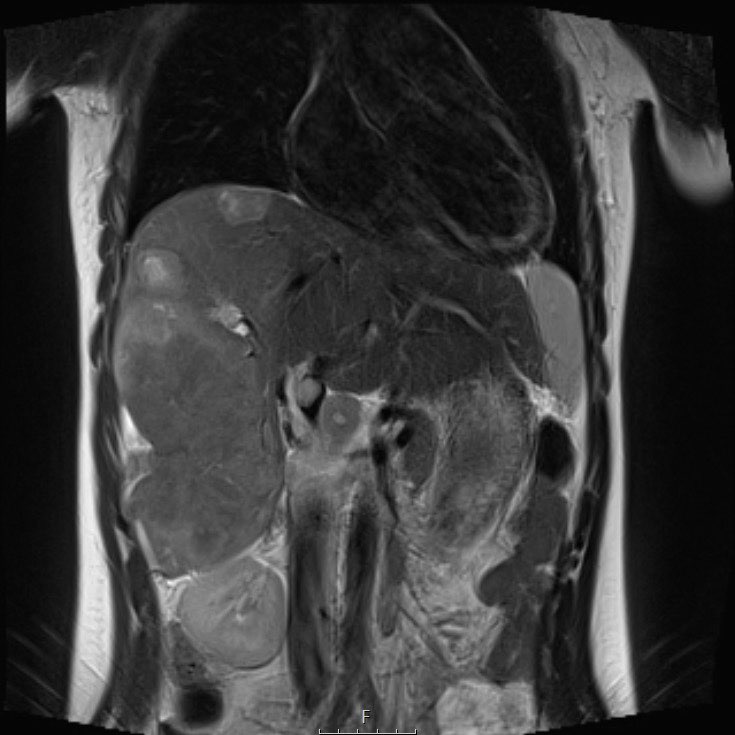

Ví dụ 1

Một bé gái ba tuổi có khối u thận trái và huyết khối khối u lớn trong tĩnh mạch thận và tĩnh mạch chủ dưới. Có di căn gan (phát hiện không thường gặp) và di căn phổi.

Video of the same patient.

Lưu ý huyết khối u trong tĩnh mạch thận trái kéo dài vào tĩnh mạch chủ dưới.